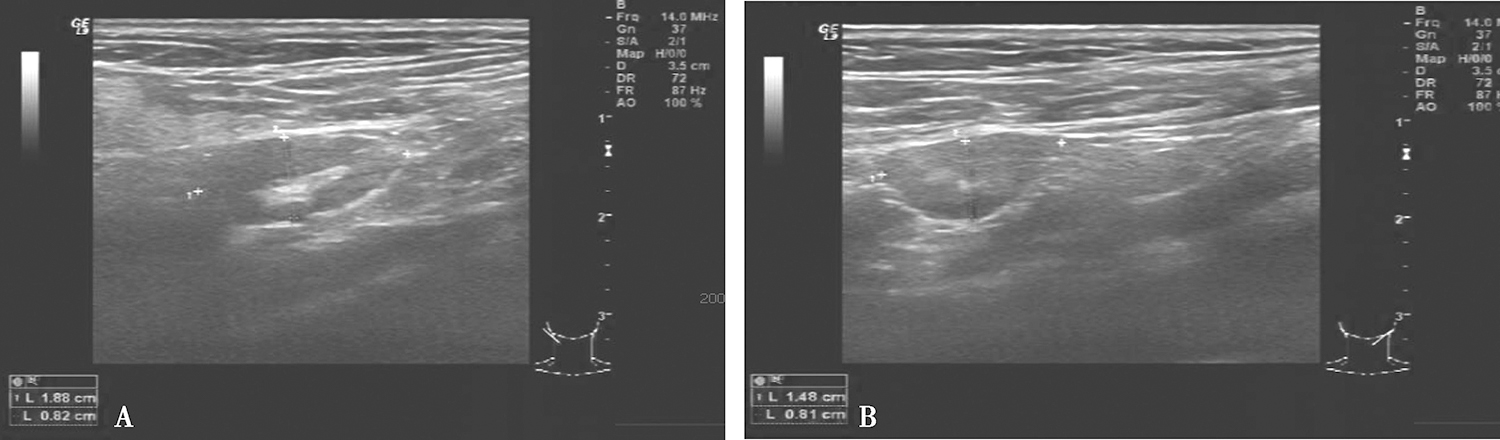

4.2016年10月8日颈部超声

双上颈、颌下及颏下见多个低回声结节,内见淋巴门结构,右侧大者约1.88cm×0.82cm(图3),左侧大者约1.48cm×0.81cm(图3),双颈未见明显肿大淋巴结。

图3颈部超声示左侧颈部低回声结节

超声诊断:

双上颈、颌下、颏下区可见淋巴结,倾向良性。